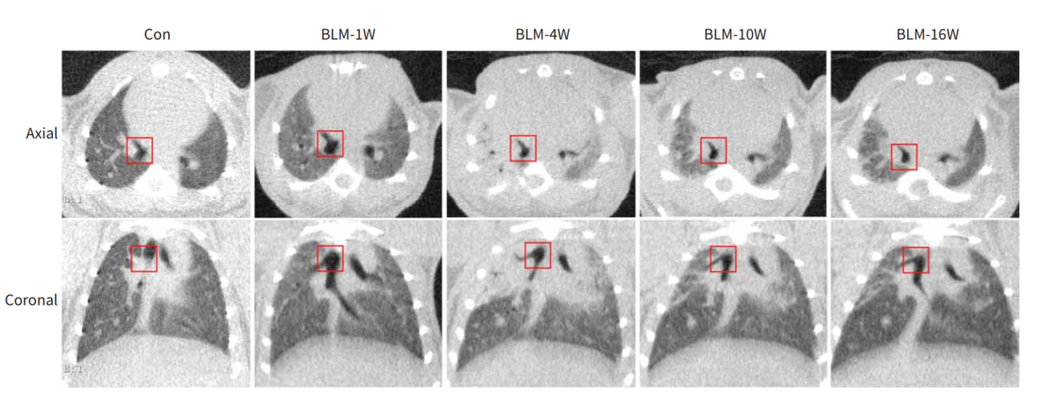

博来霉素诱导的小鼠肺纤维化模型。根据不同HU区间进行正常、低通气、不通气区域体积的分割。在第4周,结果显示低通气和不通气区域的比例都很高,然后在第10周和第16周之间明显减少,而在正常通气的区域,则呈现相反的态势。[13]

通过使用Micro-CT对小鼠肺部区域进行扫描重建成像,利用肺部分析算法(Hounsfield单位阈值范围分别为-434至-121HU和-120至121HU)实现对通气不良和非通气不良区域的影像区分,从而实现对肺部区域动态检测,并进行功能和结构的评价。量化的影像数据也能提供纵向研究的信息以减少动物之间的变异性,可以更进一步验证体外数据。

早期评估我们可以选择固定点(冠状面气管分支)位进行观察肺实质的变化,理应在造模第四周达到最大。